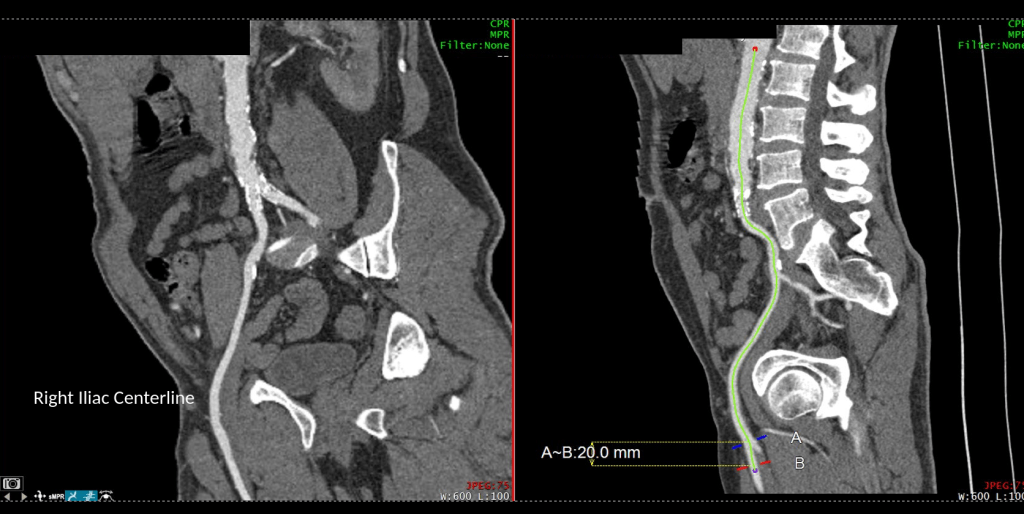

As a vascular surgeon, I perform operations in the traditional open fashion, and endovascular procedures which are a done with imaging from x-ray. Occasionally, I do laparoscopic surgery. The open surgical procedures include operations on the aorta and its branches, and on arteries in the legs, arms, and neck. I also work on veins throughout the body. The patient arrives with a set of conditions, a prior history, and an examination, and given a problem, you evaluate it with various tests which can be blood tests, vascular tests, imaging studies like X-ray, Ultrasound, Vascular Lab Studies, CT scans and MRI’s. This is called the workup -getting data to plan a procedure. Knowledge of anatomy and physiology and biomechanics of flow are crucial to put together a plan that will be successful in treating the disease with low complication rate and good durability. The procedures require a great deal of planning and often I include my colleagues within my department and those in other specialties to get their insights for making a plan that accounts for the reason for operation, plan for operation, contingency plans, and recovery in the hospital, and healing outside the hospital. You can see some of these cases on my blog, vascsurg.me.